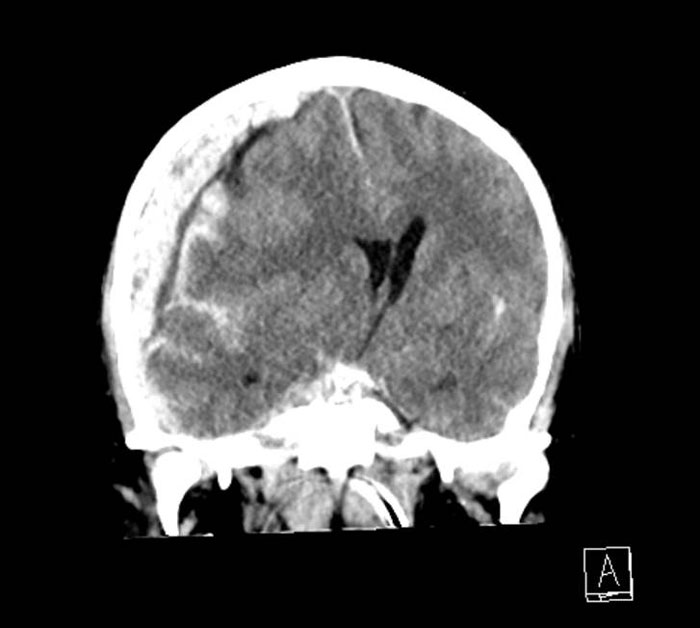

Kvinna sparkad av häst. Patienten inkom till akuten med en öppen sårskada ovan höger öra. Hennes RLS-nivå var 3.

Datortomografi visar en komminut impressionsfraktur med underliggande kontusionsblödning.

Bilder från neurokirurgiska kliniken, Universitetssjukhuset i Linköping.